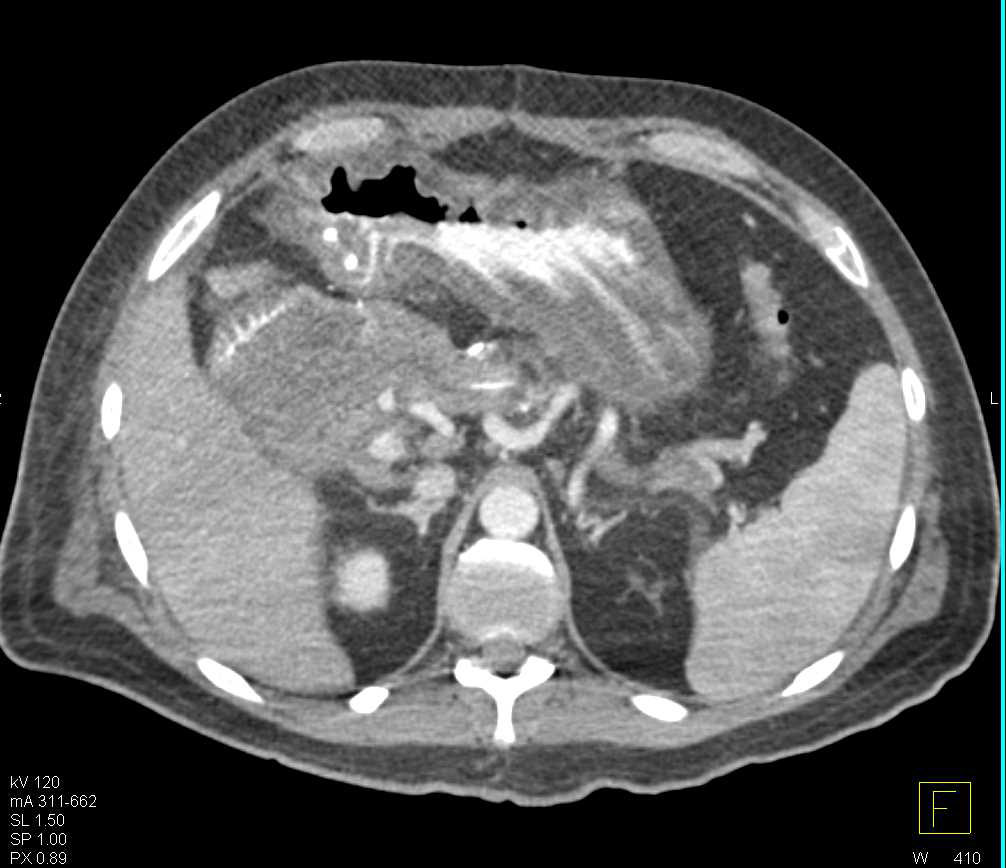

Carcinomatosis with Implants in Abdomen and Pelvis